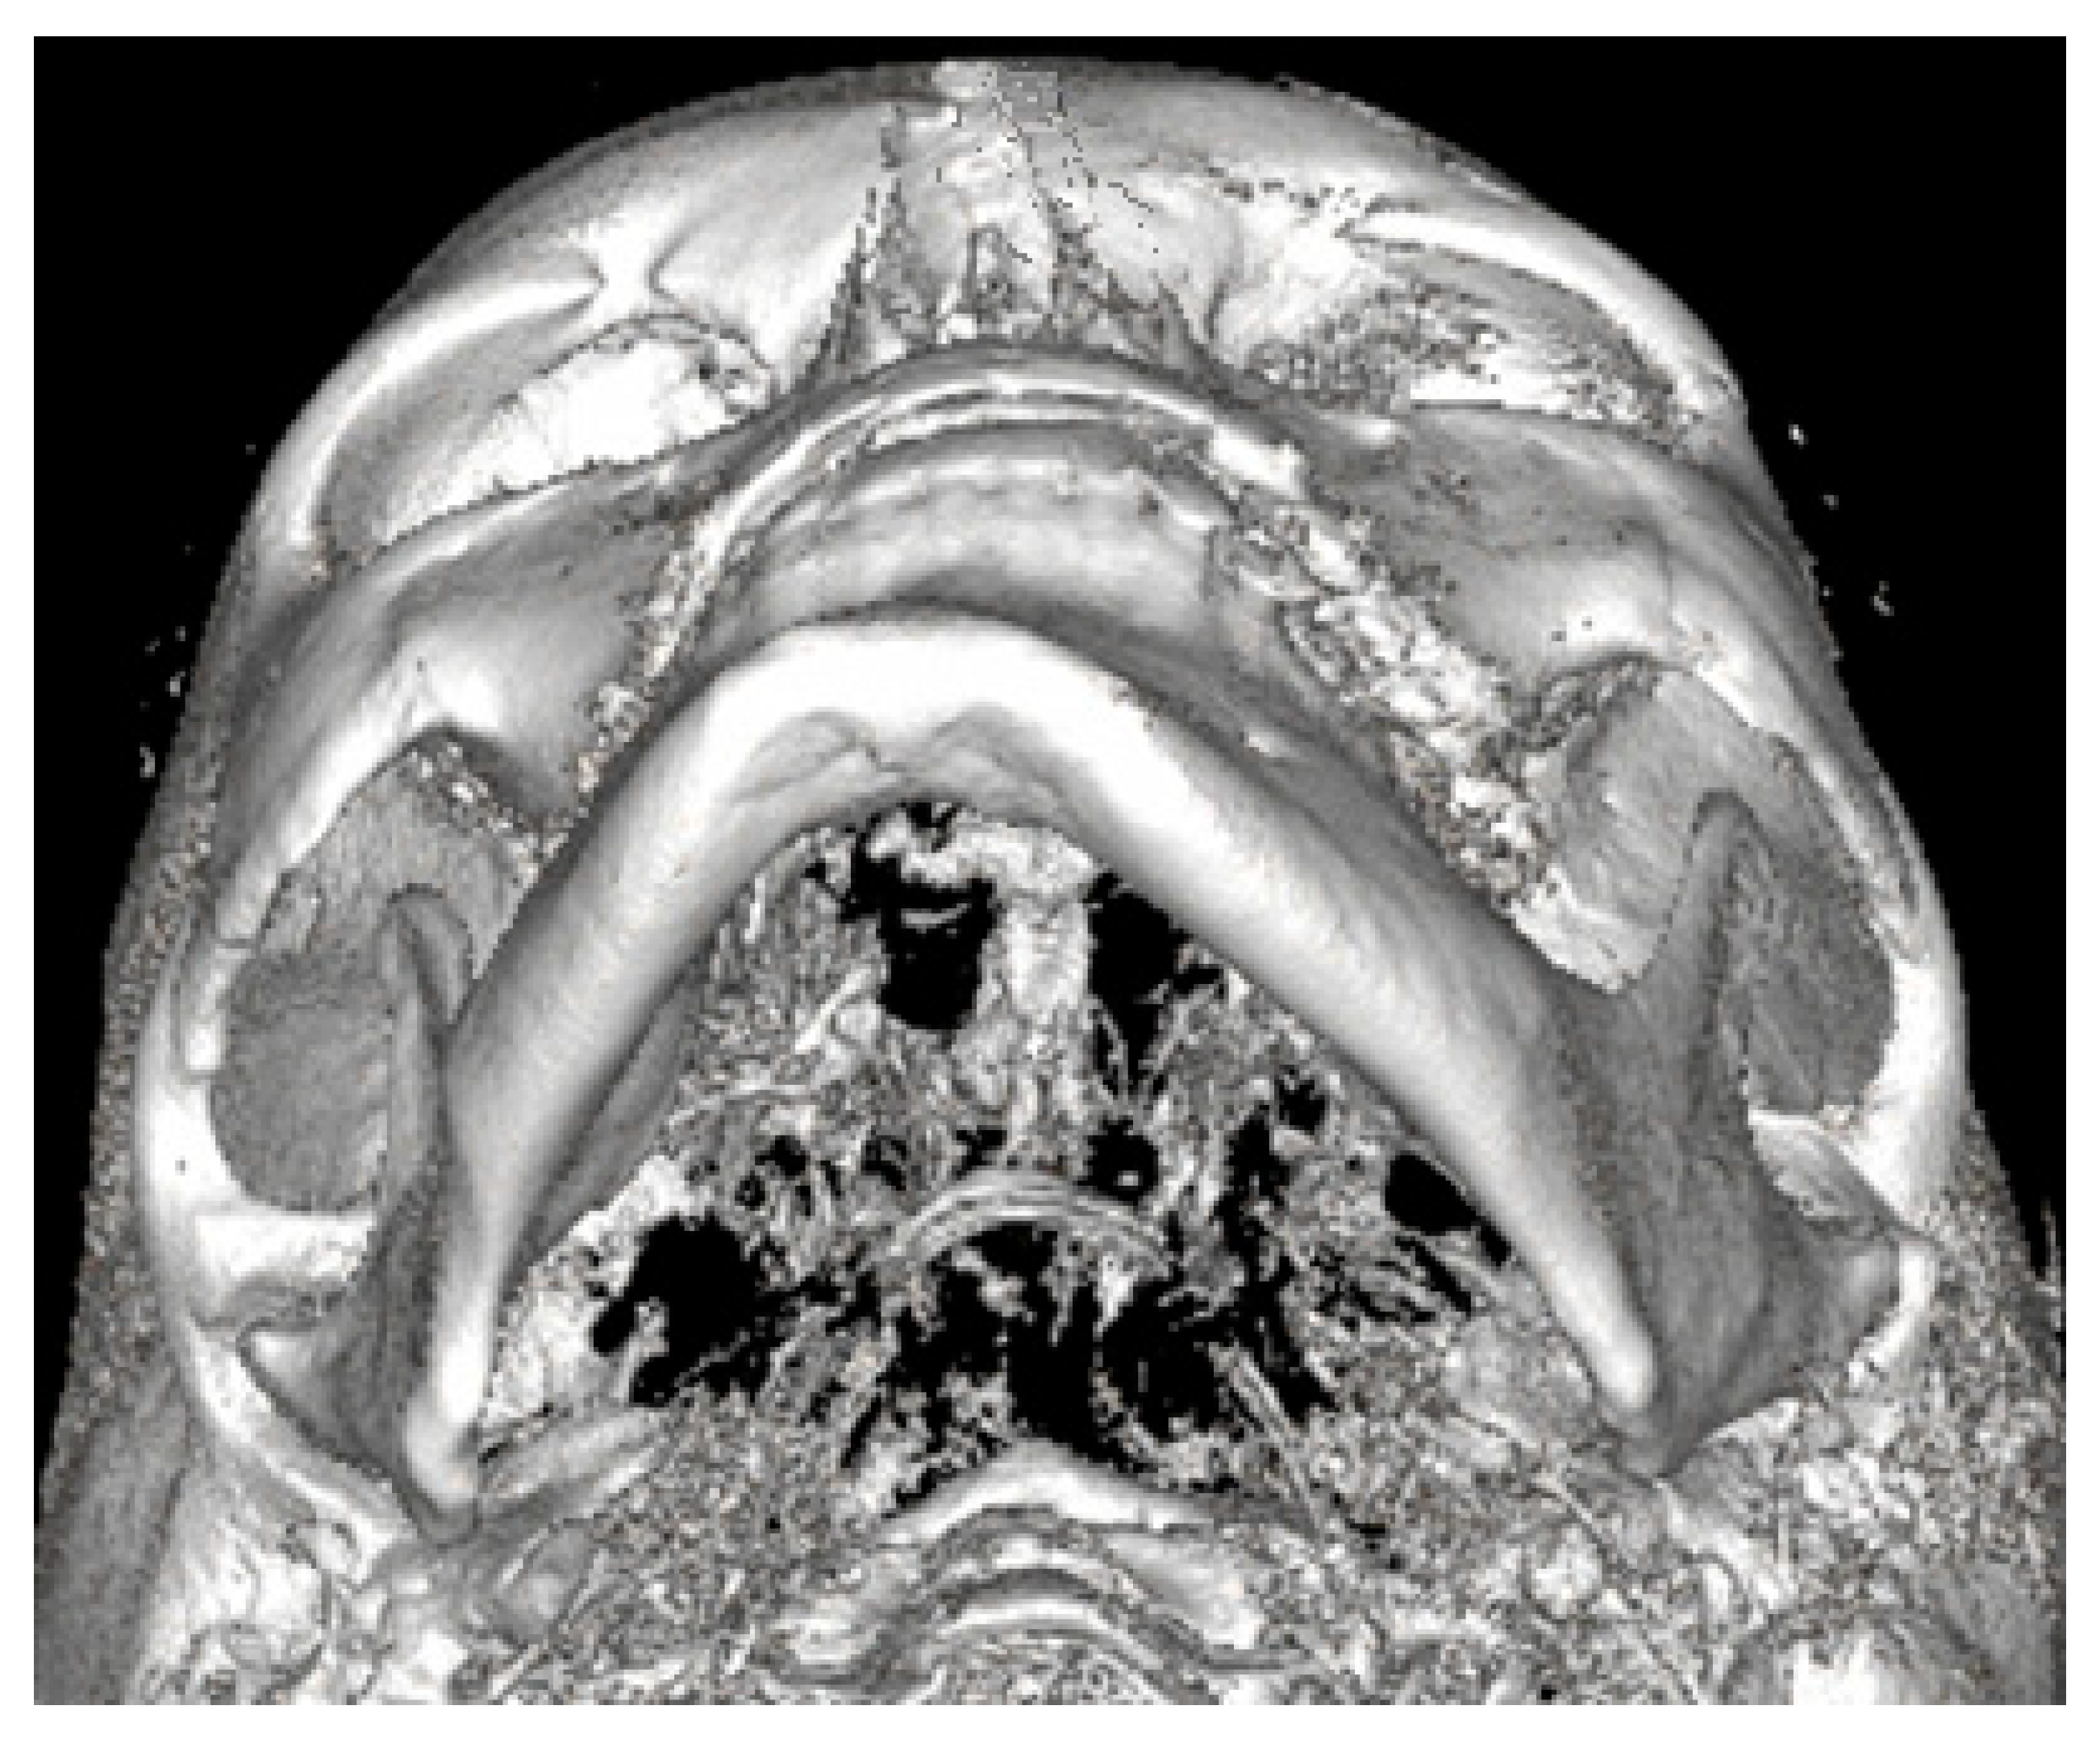

3.4. Low-Dose Computer Tomography

Both panoramic radiographs and LDCT evaluations are important for any surgery planning. There is a possibility to estimate the shape and position of the mandibular canal while tracing its course on 3D evaluation and then estimating the degree of surgery in MIB (Figure 3 and Figure 4). Secondly, based on the studied patients’ data, the authors also include that the position of the mental foramina, chin deviation, and Go reference points described herein are valuable reference points for future surgical planning. Another important feature possible to estimate on 3D-LDCT is the scope of mandibular basis overgrowth in three dimensions.

Figure 4.

LDCT semi-axial view on the deviated mandible. Except for chin deviation, elongation of left mandibular basis, and slight Go-point asymmetry, the mandibular body is not enlarged nor presents overgrowth in a significant diameter.

The usage of a 2D-panoramic radiograph is helpful. More important measurements nowadays are made on 3D-virtual planning models (Figure 5). 3D planning might improve surgeons’ insight and the scope of bone evaluation. Because of great improvements in surgical planning, not only 3D-CT/LDCT evaluation is helpful. The usage of 3D stereolithographic models is an alternative method, where surgical cuts and plate bending might be quite easily made before surgery to ensure that the selected surgical approach is the most adequate of all. In cases of asymmetry visualized in patients in face view after orthognathic, surgical, and orthodontic treatment, some detailed total mandibular symmetry correction protocols are needed. Direct 3D-LDCT planning based on the used anatomical reference points presented herein is helpful in restoring facial balance and mandibular symmetry (Figure 6 and Figure 7). The authors’ future studies will focus on the 3D evaluation of facial skeleton, soft tissue changes in CT/MR, and lateral profile alterations; because of that, any other data are excluded from this study.